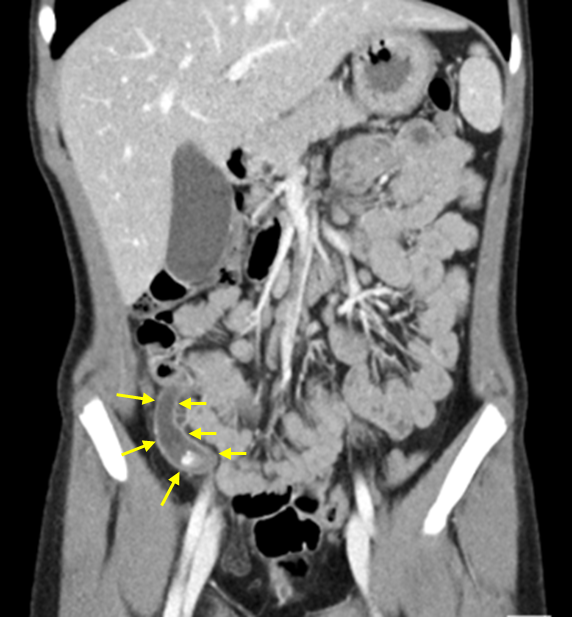

10세 남아가 1일 전에 발생한 복통으로 병원에 왔다. 어제 오후부터 배꼽 주위에 복통이 생겼다. 속이 불편해서 밥을 평소보다 적게 먹었으며, 오늘은 오른쪽 아랫배가 아프고 한 번 토했다고 한다. 혈압 110/74 mmHg, 맥박 110회/분, 호흡 24회/분, 체온 36.8℃이다. 배 진찰에서 장음은 정상이나, 오른쪽 아랫배에 복부강직, 압통과 반발통이 있다. 복부 컴퓨터단층촬영 사진이다. 혈액검사 결과는 다음과 같다. 진단은?

Img | CT: 결석을 동반한 막창자꼬리염 소견 |

• CT에서 appendicolith를 동반한 충수돌기염 소견이 있어 확진할 수 있다.